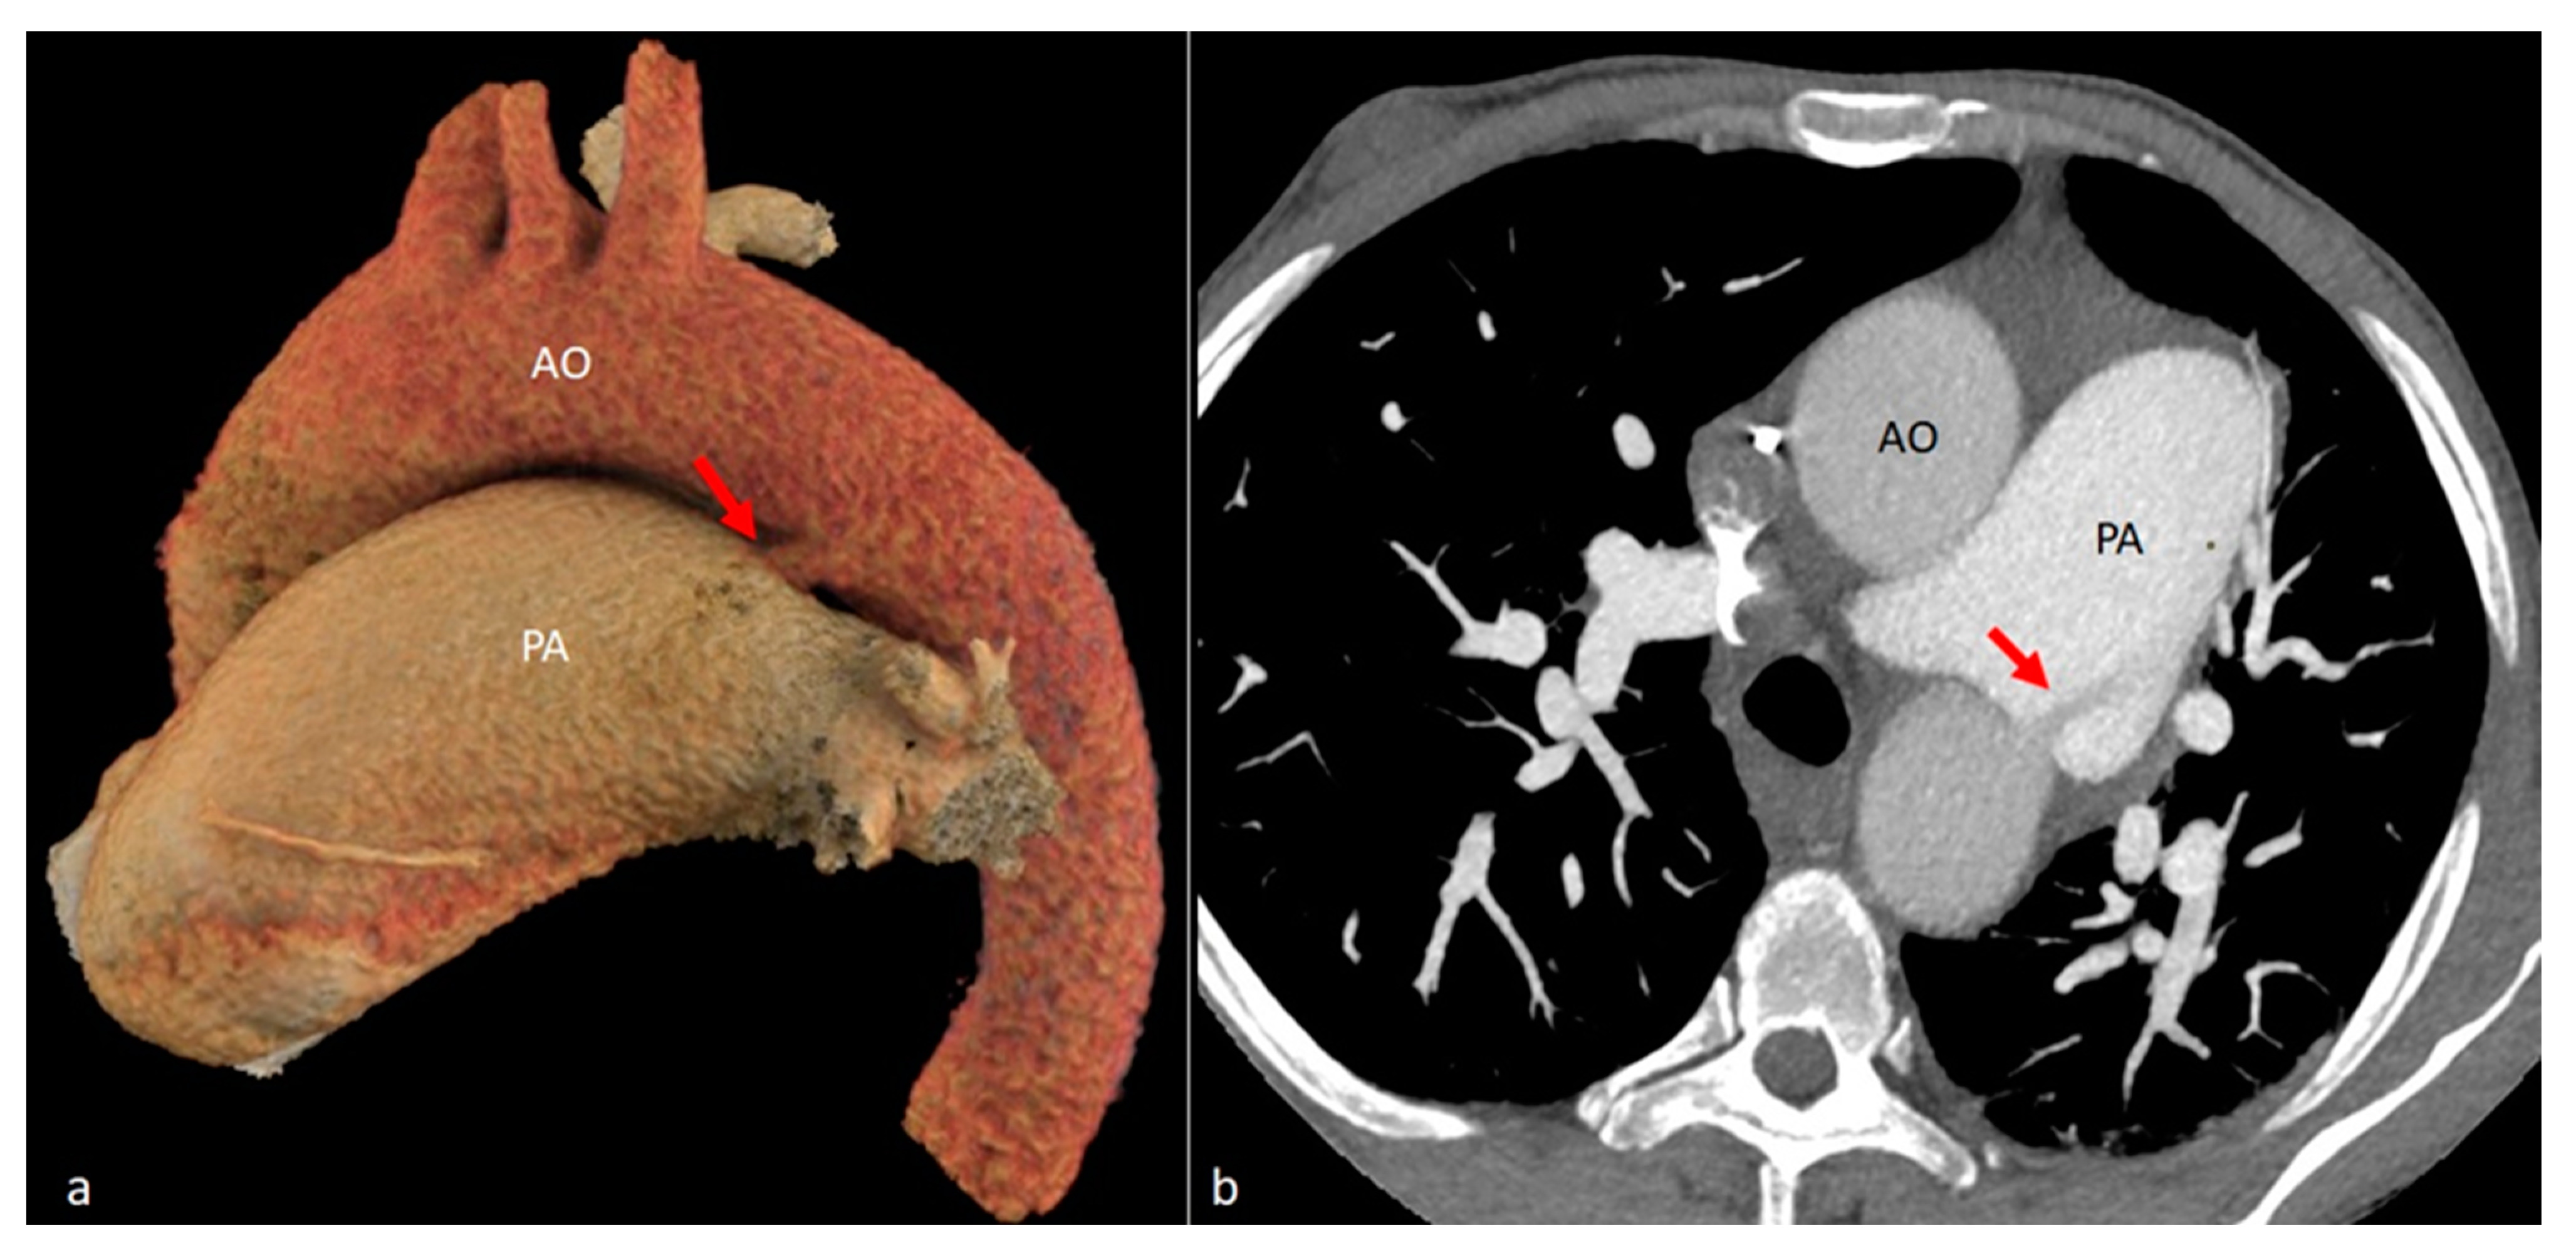

| AO | Aorta |

| PA | Pulmonary artery |